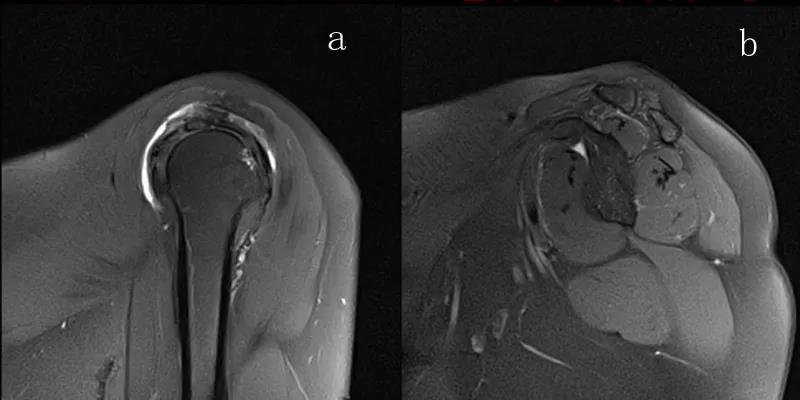

图24 a.肩袖全层撕裂;b.正常MRI

图25 巨大肩袖损伤(冈上肌)